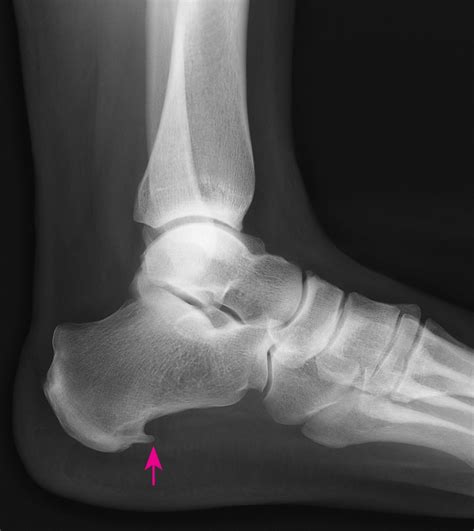

A bone spur, medically known as an osteophyte, is a bony growth that develops along the edges of a bone. When it occurs in the heel, it is typically located either on the underside of the heel bone (calcaneus) or at the back of the heel near the Achilles tendon. These growths occur as the body’s response to long-term stress, pressure, or inflammation.

The development of bone spurs in heel is often a slow, gradual process. As your body attempts to repair injured or stressed areas, it deposits extra bone material. Over time, this results in a visible or palpable bump. It is important to note that the spur itself is not always the direct source of pain; rather, it is often the surrounding tissue inflammation that causes discomfort.

Recognizing the signs of this condition is crucial for timely management. Many people live with bone spurs without even knowing it until an X-ray reveals them. However, when symptoms do arise, they can be quite debilitating.